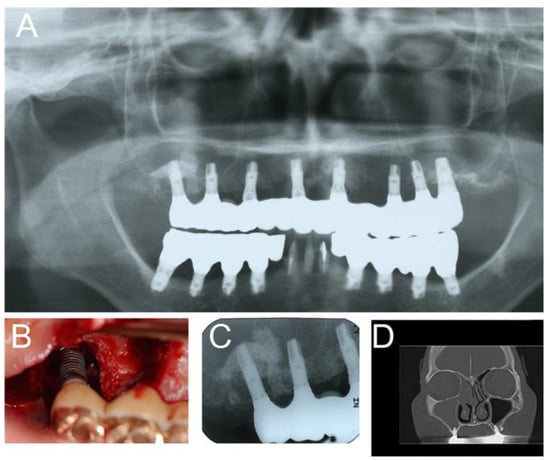

Severe peri-implantitis may cause chronic maxillary sinusitis (Figure 3). The dental causes of peri-implantitis include poor oral hygiene, persistent/recurrent periodontitis, and so on [10]. Therefore, we think that peri-implantitis can be a possible causal/risk factor for postoperative complications after implant surgery.

Figure 3. Severe peri-implantitis in the upper right molar region was observed 10 years after implant therapy with sinus augmentation. (A) Panoramic radiography; (B) oral photograph; (C) intraoral radiograph; (D) paranasal CT shows right rhinosinusitis. In this case, chronic maxillary sinusitis occurred through the pathway from peri-implantitis to the maxillary sinus for a long period. Therefore, FESS was performed (unpublished data).